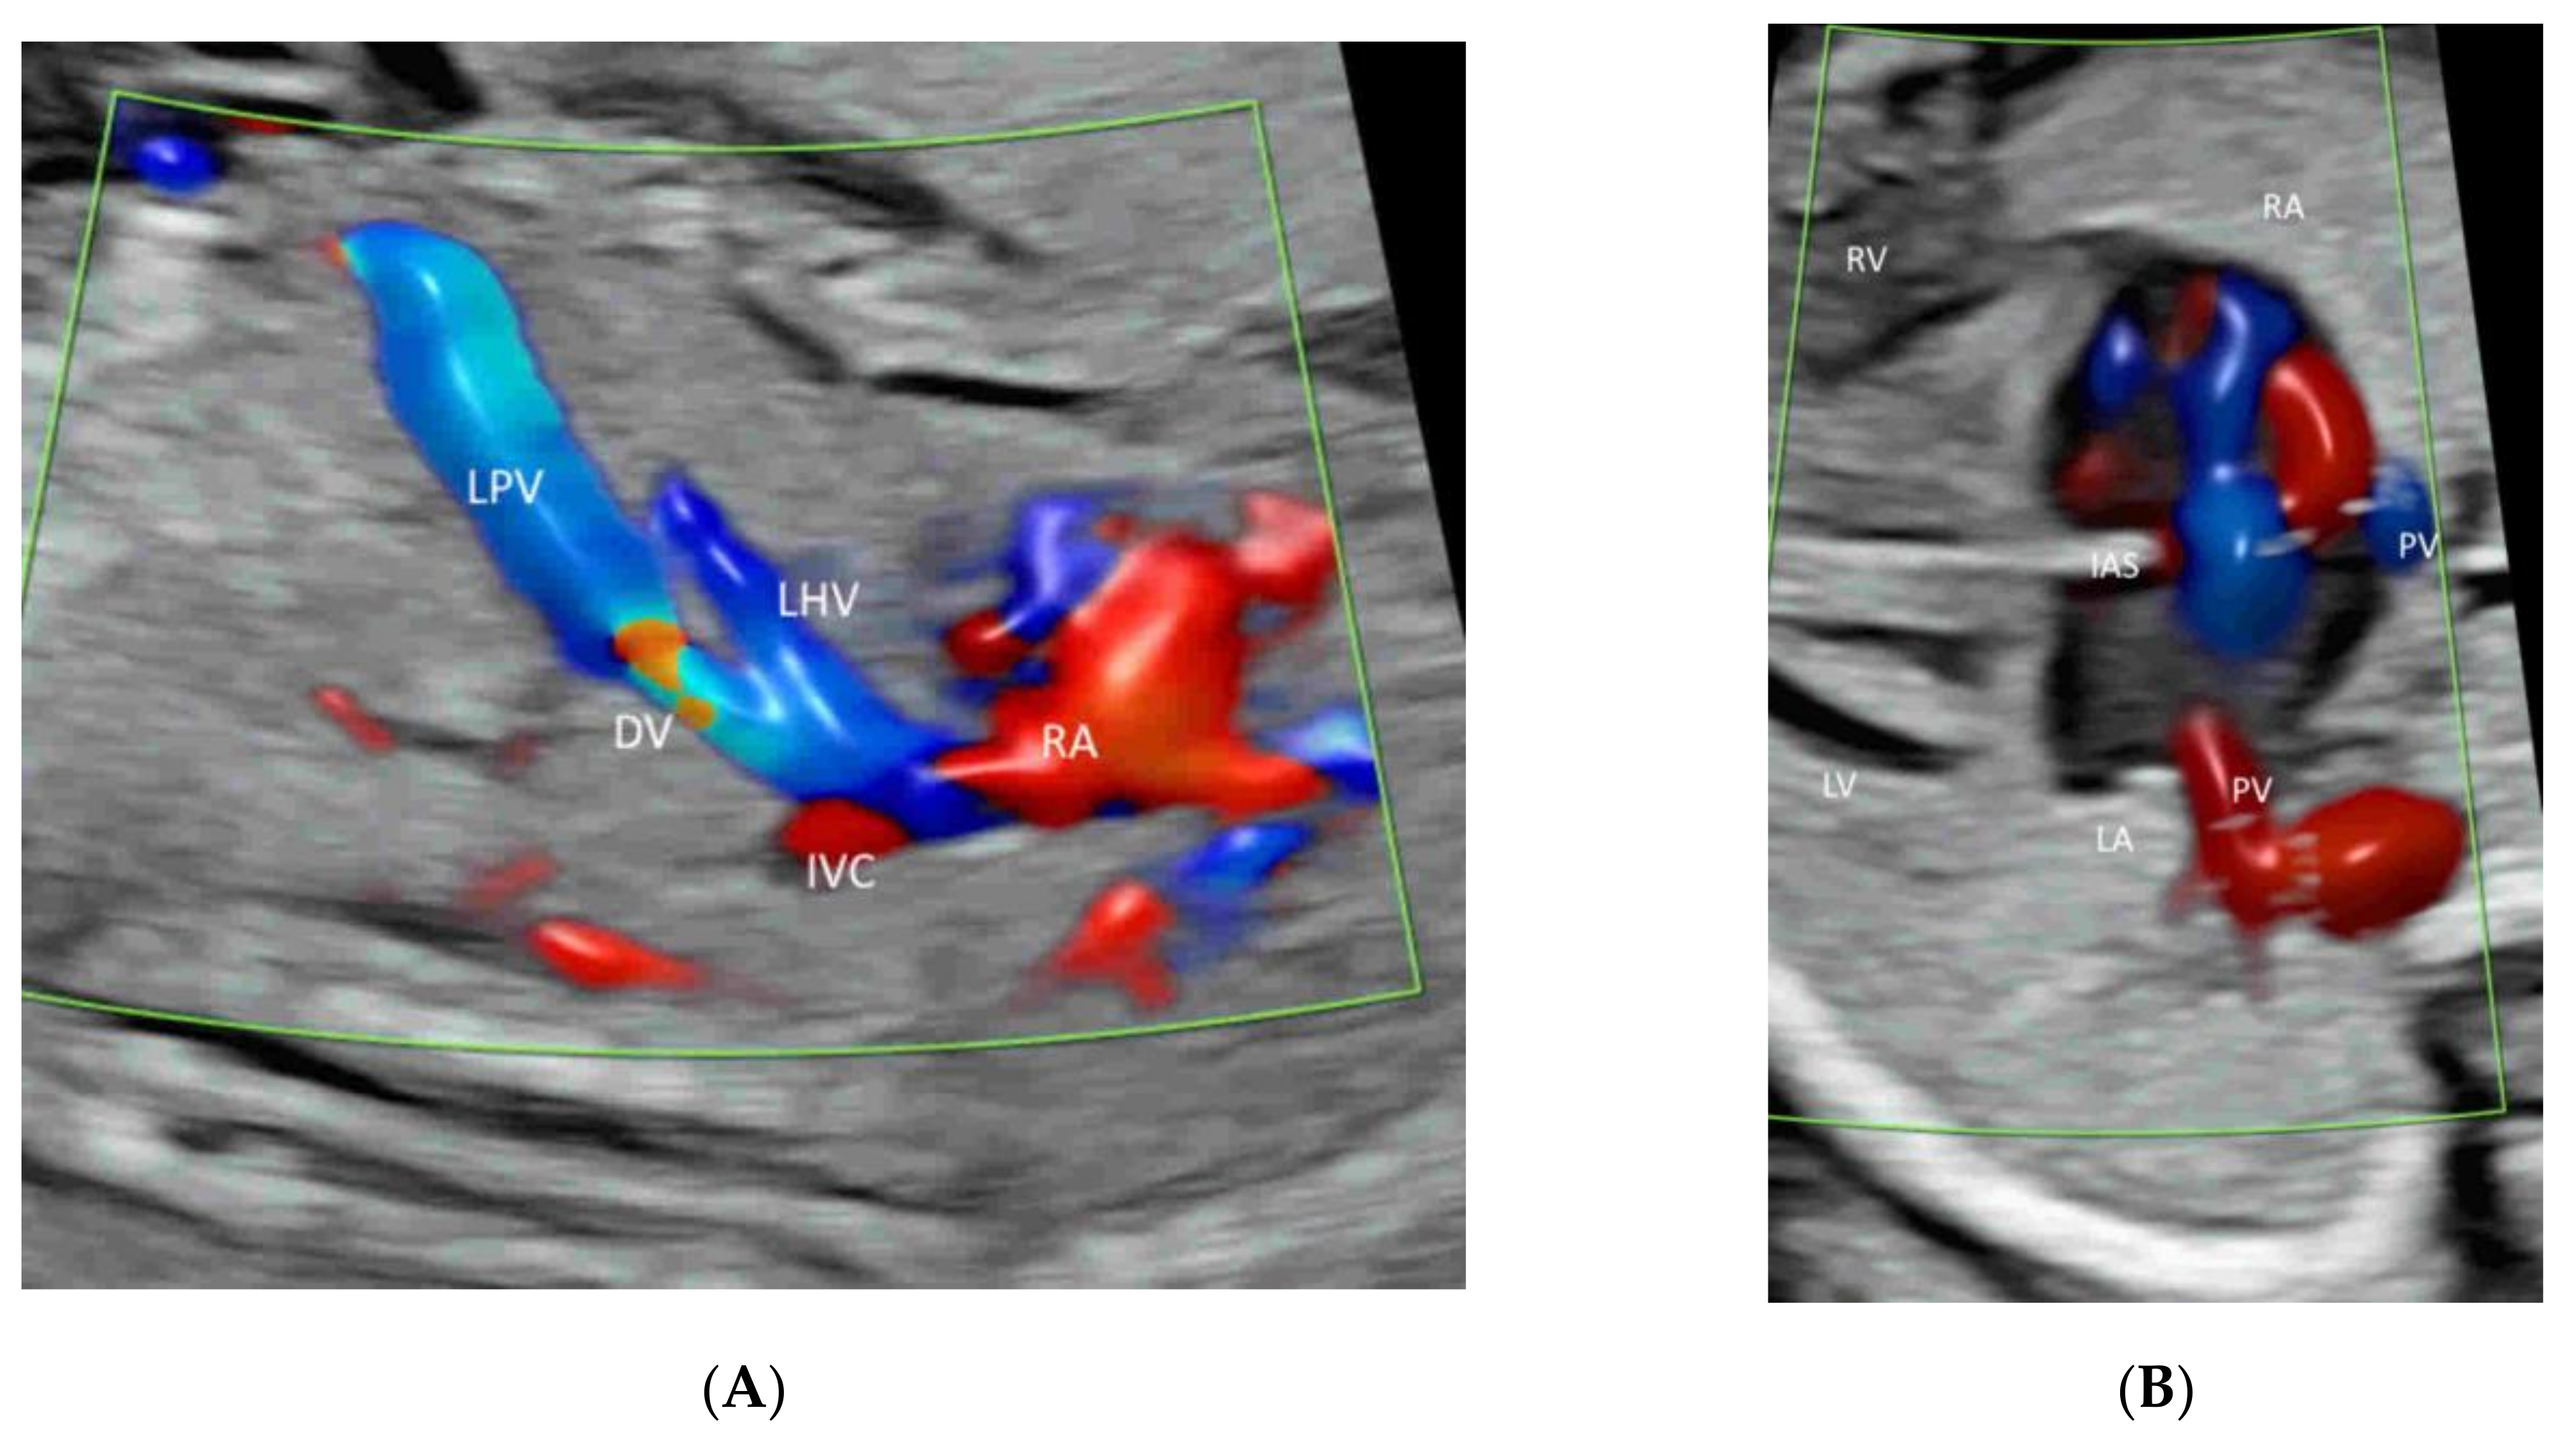

- Yagel, S.; Cohen, S.M.; Valsky, D.V.; Shen, O.; Lipschuetz, M.; Messing, B. Systematic examination of the fetal abdominal precordial veins: A cohort study. Ultrasound Obstet. Gynecol. 2015, 45, 578–583. [Google Scholar] [CrossRef] [Green Version]

- Yagel, S.; Cohen, S.M.; Valsky, D.V. Simplifying imaging of the abdominal fetal precordial venous system. Ultrasound Obstet. Gynecol. 2019, 53, 571–575. [Google Scholar] [CrossRef]

- Leung, K.Y. Imaging of fetal precordial venous system by four-dimensional ultrasound with spatiotemporal image correlation technology. J. Clin. Ultrasound 2021. [Google Scholar] [CrossRef]